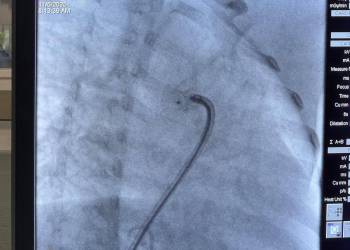

Katharina Kaufmann and Katrin Krüger, Administrative Directors of the German International School Accra (GISA), visited the current project of the Gerald Asamoah Foundation for Children with Heart Disease at the Korle Bu Teaching Hospital in Accra.

Both were deeply impressed by the professionalism, dedication, and compassion of the entire team. For many years, the foundation has supported children in Ghana with congenital heart defects – providing them with life-saving surgeries and renewed hope.

“Yesterday I had the privilege to observe the doctors and nurses of the Gerald Asamoah Foundation for Children with Heart Disease at work in the Korle Bu Teaching Hospital. I have great respect for the incredible work they do – with such commitment, professionalism, and heart. I was truly moved.💖”

“I am deeply impressed by the outstanding work of the Gerald Asamoah Foundation. What the doctors and nurses achieve here deserves the highest respect. It especially touched me to see that many of the children are around the same age as my own – it really goes under your skin.”